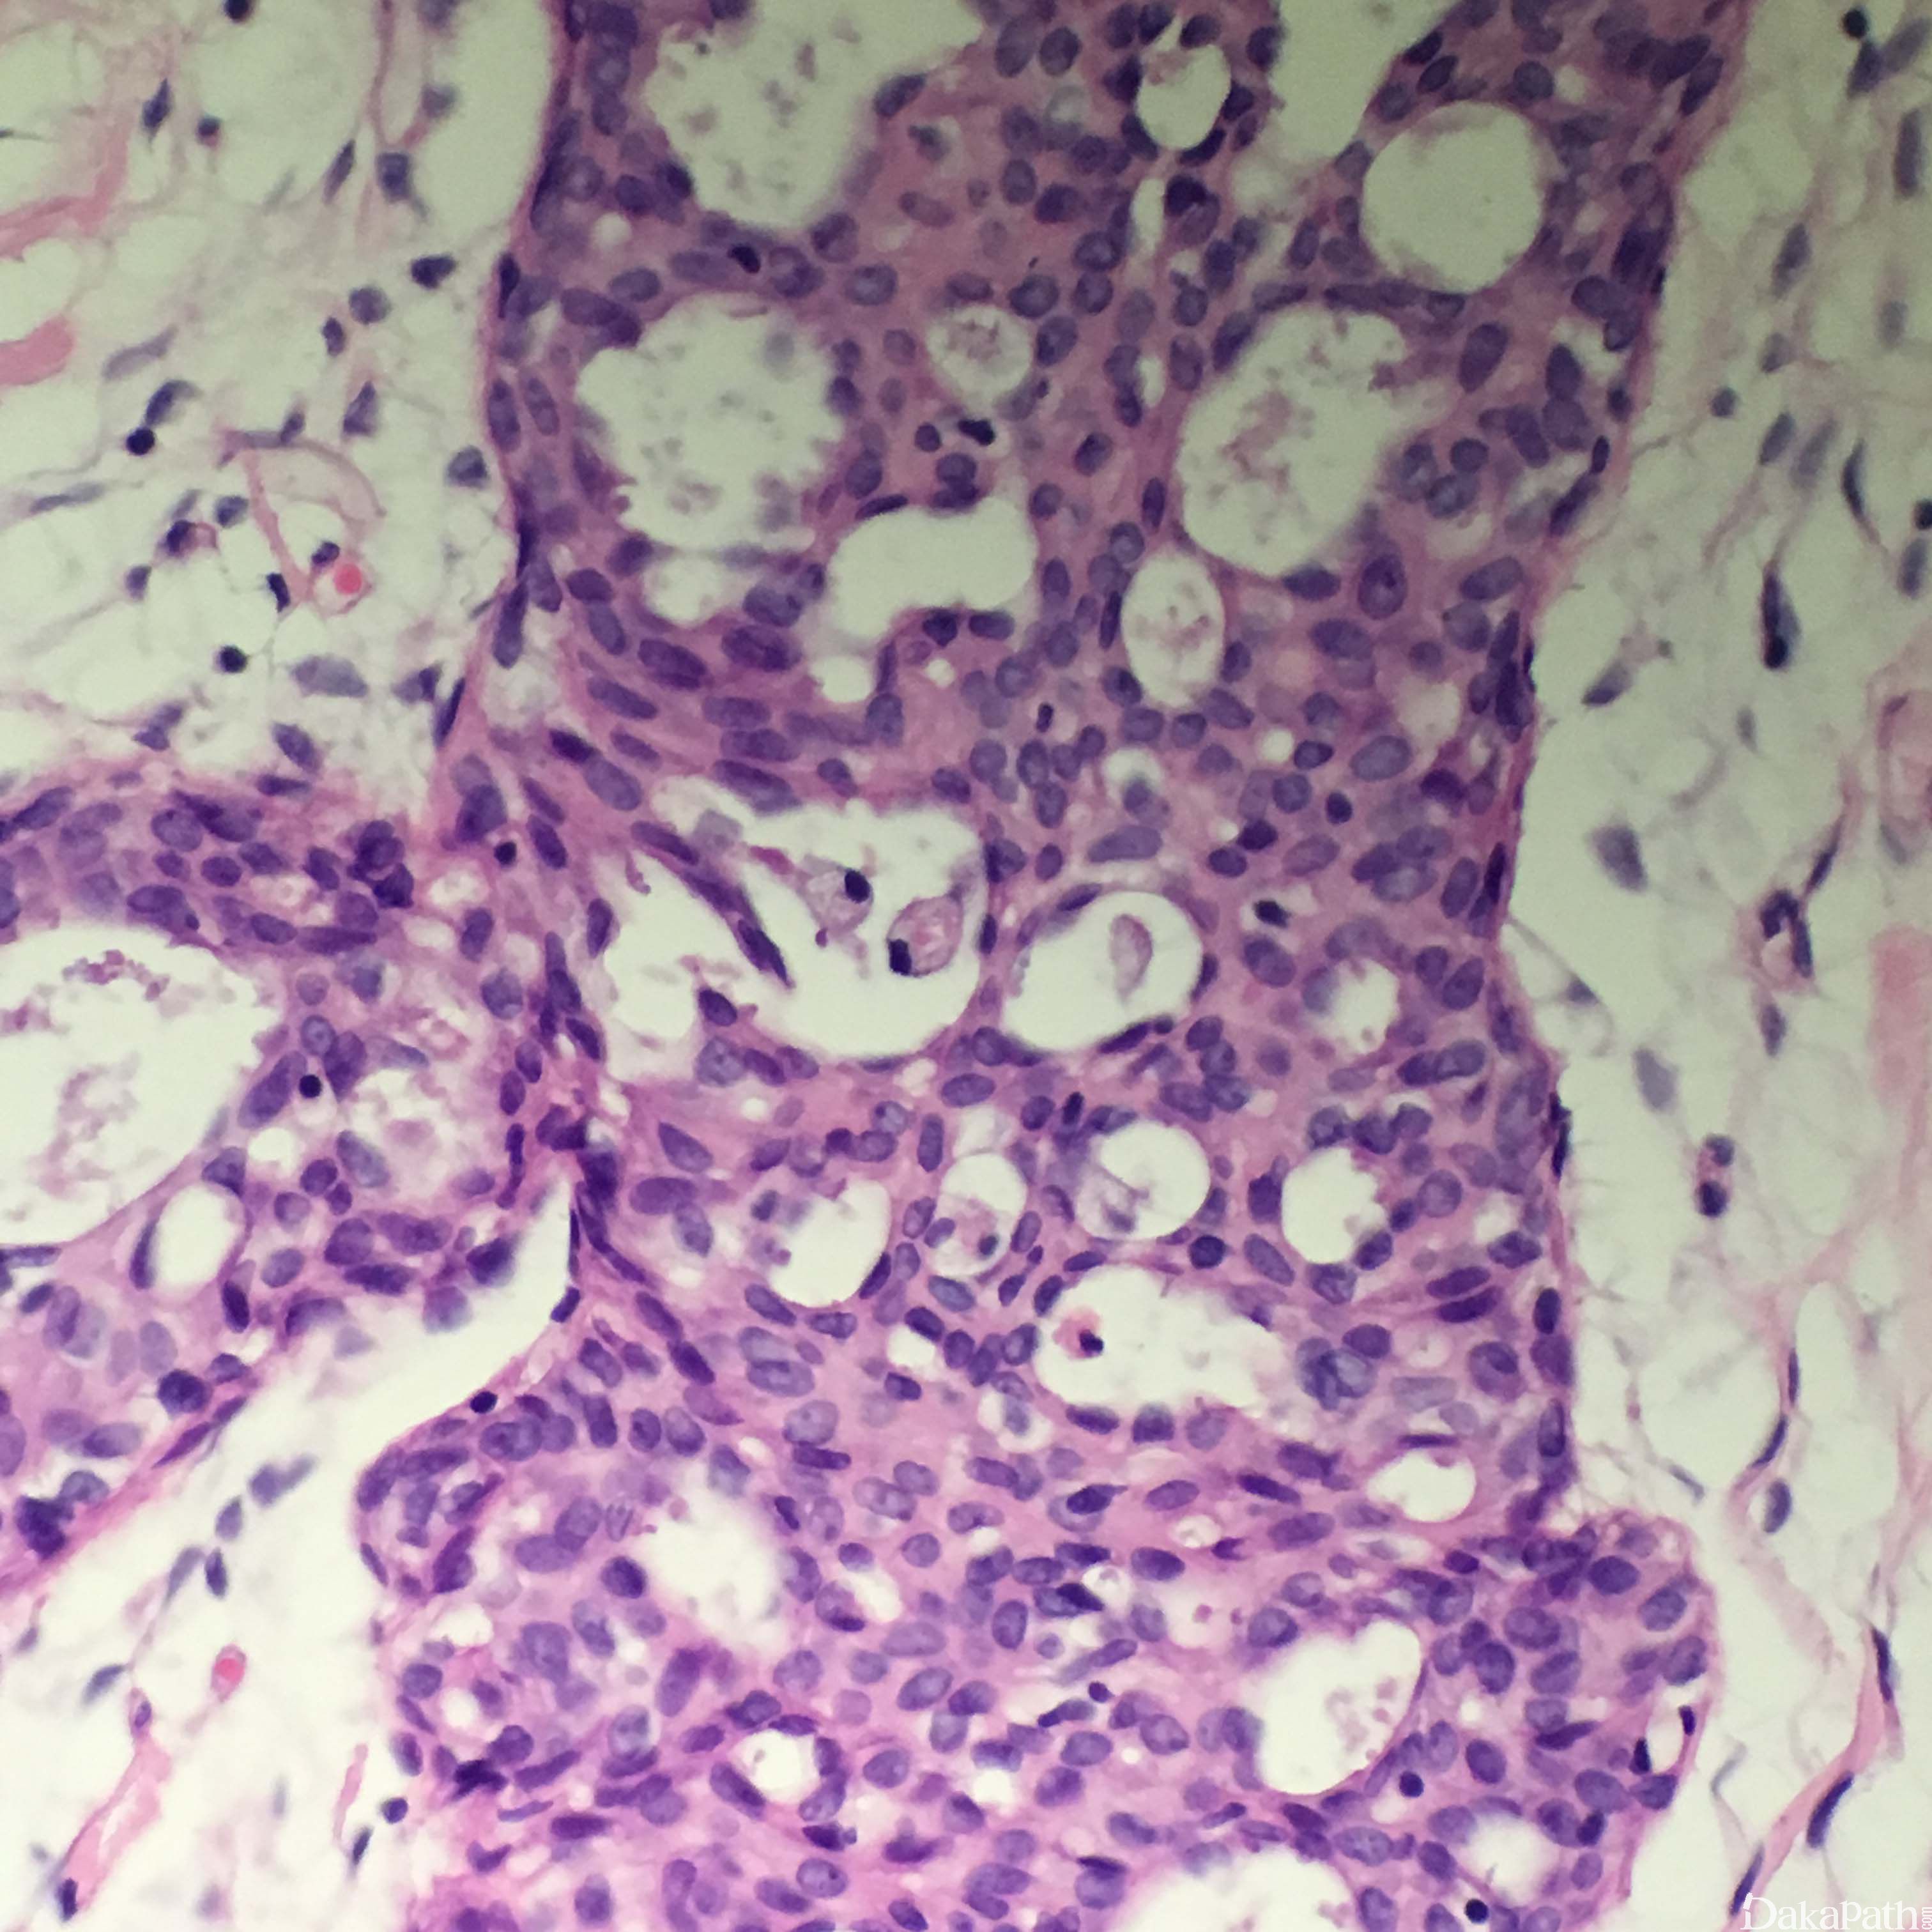

- 组织学结构特征:超过正常的乳腺的两层结构(肌上皮细胞和腺上皮细胞层),细胞杂乱的紧密增生。轻度增生是指 2-4 层增生的腺细胞,旺炽性增生是指大于 4 层增生的腺细胞,可以形成实性的、筛状的或微乳头结构。

- 实性型 UDH 表现细胞大小不等、形状各异,排列杂乱,可以出现导管周围裂隙样的空隙,肌上皮细胞层存在;

- 多孔型 UDH 表现为形成孔的腺腔不规则,腺腔大小和形状各异,经常裂隙样并出现在导管周围,和 ADH 及低级别 DCIS 中看到的圆形的、穿凿样的腺腔不同,不显示围绕腺腔的极向,排列杂乱、可以重叠;有些病例表现为梭形的腺细胞呈明显的流水样或旋涡状排列;

- 细胞学特征:可以有合体细胞特征,单个细胞的边界不清;细胞是多克隆增生,而不是单克隆增生;细胞大小、形状及核方向多样,常见核沟及核内包涵体;偶尔可以看到核分裂;有时可以看到中心坏死,特别是在增生非常旺盛的区域;可以存在大汗腺化生或透明细胞化生,而且存在这些化生往往说明是良性改变而不是 ADH 或 DCIS。